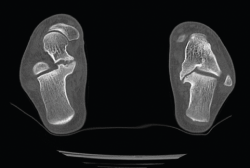

Figura 1. Fractura conminuta de la cúpula del astrágalo.

Se trata de un paciente varón de 35 años que, tras una precipitación, presenta impotencia funcional en el miembro inferior. Tras la valoración clínica y radiológica, se observa un estallido de la parte posterior de la cúpula astragalina (Figura 1).